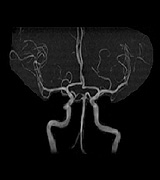

MRI画像

• mri01

• mri02

• mri03

• mri04